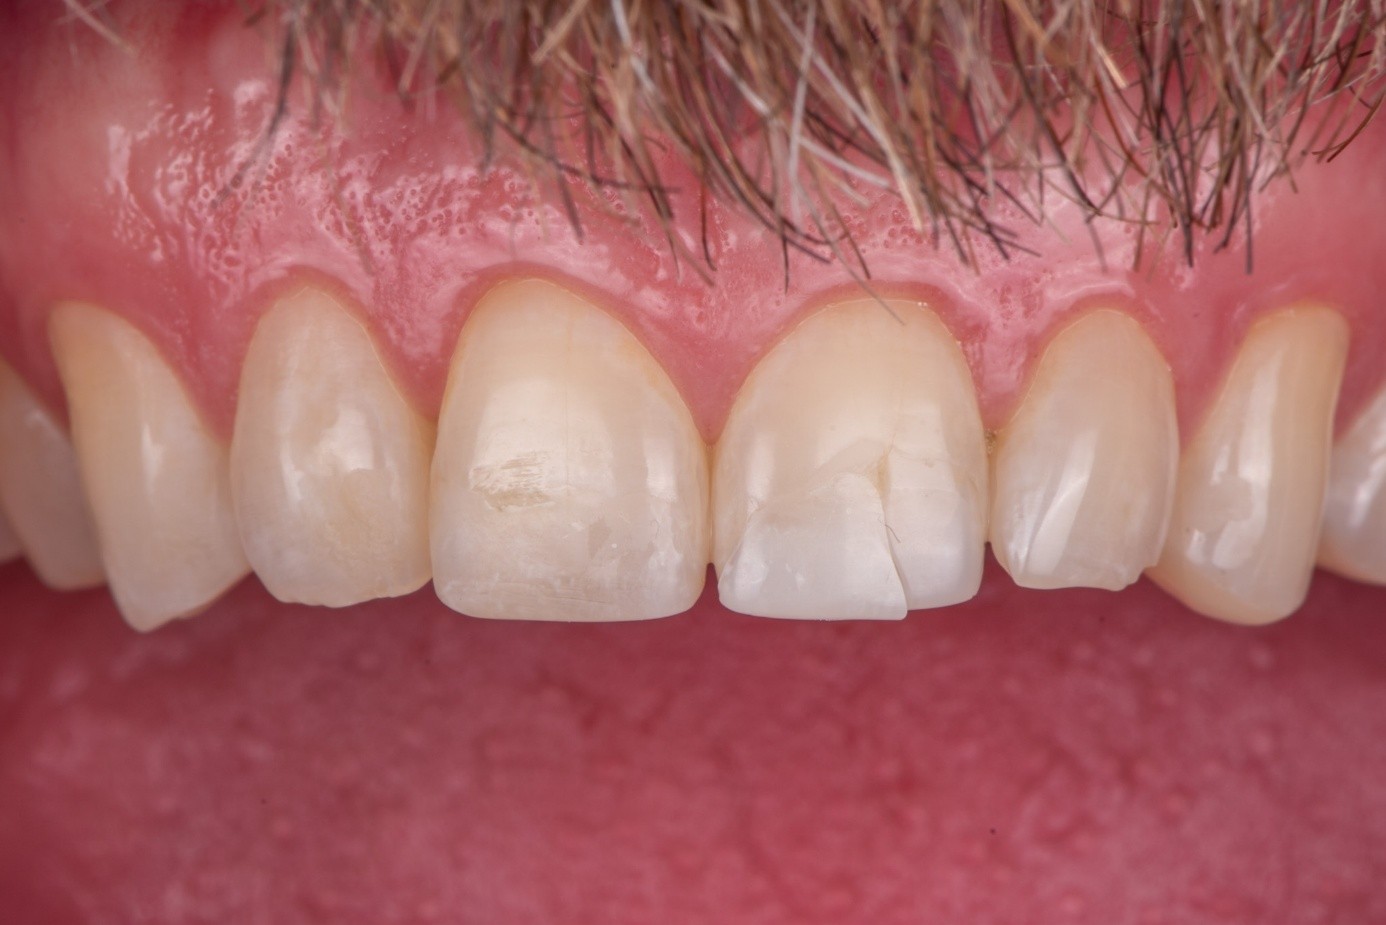

Case 2: Composite Facing Fracture

This case involved a patient with generalized mild anterior wear and an existing composite restoration on the maxillary left central incisor. The restoration extended from the middle third to the incisal edge and had excellent shade match and no marginal discoloration. The patient presented with a fractured central mesial portion of the composite (Figure 14 through Figure 16). Examination revealed a mixed failure pattern: Some adhesive and composite remnants remained on the tooth surface, while the fractured piece showed no residue internally. This finding suggested that the weak point was at the interface between composite and adhesive layer, with a minor cohesive component within the composite itself (Figure 17).

From a clinical standpoint, this pattern is reassuring, as it indicates a strong bond to the tooth substrate and that the restoration had functioned successfully until the composite material itself reached its fracture threshold. Considering the generalized wear pattern and patient history, parafunctional habits were suspected as the main cause of failure—the composite likely fractured when the applied functional stress exceeded its material strength.

(14.) Intraoral view showing the fractured ceramic fragment positioned in place. The piece fits well, although minor gaps are present between the margins due to slight material loss, which can be restored using luting composite.

Figure 14

(15.) Intraoral view showing the fractured ceramic fragment positioned in place. The piece fits well, although minor gaps are present between the margins due to slight material loss, which can be restored using luting composite.

Figure 15

(16.) Intraoral view showing the fractured ceramic fragment positioned in place. The piece fits well, although minor gaps are present between the margins due to slight material loss, which can be restored using luting composite.

Figure 16